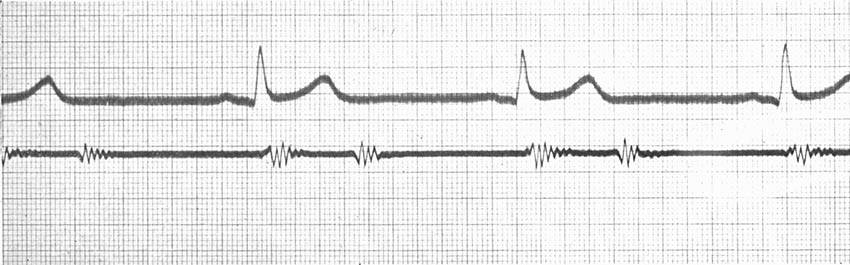

| Continuous Moving-picture Records of Heart-beats | 136 |

| Continuous Moving-pictures of Heart-beats of an Excited Person | 137 |

| Continuous Cinematography—Palpitations of a Rabbit's Heart | 142 |